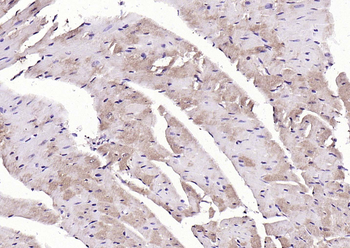

100 μl, 200 μl, 50 μl - LATS2 Rabbit Polyclonal Antibody [orb6306]Featured

IF, IHC-Fr, IHC-P, WB

Human, Mouse, Rat

Bovine, Canine, Equine, Gallus, Rabbit

Rabbit

Polyclonal

Unconjugated

100 μl, 200 μl, 50 μl - Featured